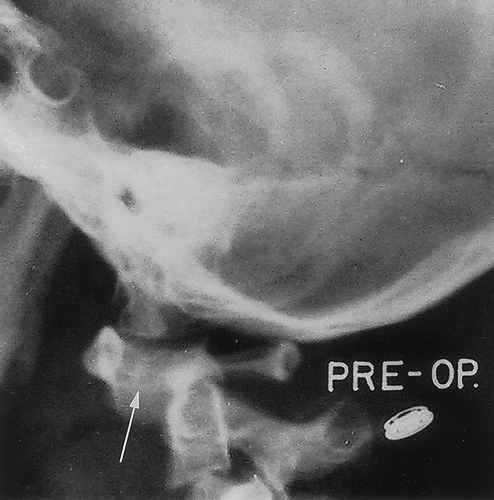

• Signs of intussusception on plain film:

• Target sign

• This radiograph shows a classic target sign in the right upper quadrant just below the liver. It resembles a chubby doughnut with a puffy center. It is very subtle. This radiograph also shows the absent liver edge sign and the crescent sign. A paucity of bowel gas is also noted.

• Crescent sign

• Soft-tissue density mass of the intussusceptum projecting into the colon (leading edge). If the head of the intussusceptum is projecting into a gas filled pocket, it will show itself. It often takes on a crescent shape; however, it may also merely resemble a protruding head into a gas filled pocket.

• This radiograph shows a classic crescent sign in the left upper quadrant. This radiograph indicates that the head of the intussuception is in the distal transverse colon. Also note that this radiograph demonstrates the target sign and the absent liver edge sign.

• This radiograph shows an atypical crescent sign in the right upper quadrant just below the liver. The head of the intussusception is coming up the ascending colon. It can be seen protruding upward into the gas filled transverse colon at the hepatic flexure.

• Absent liver edge sign

http: //www.hawaii.edu/medicine/pediatrics/pemxray/v1c02.html